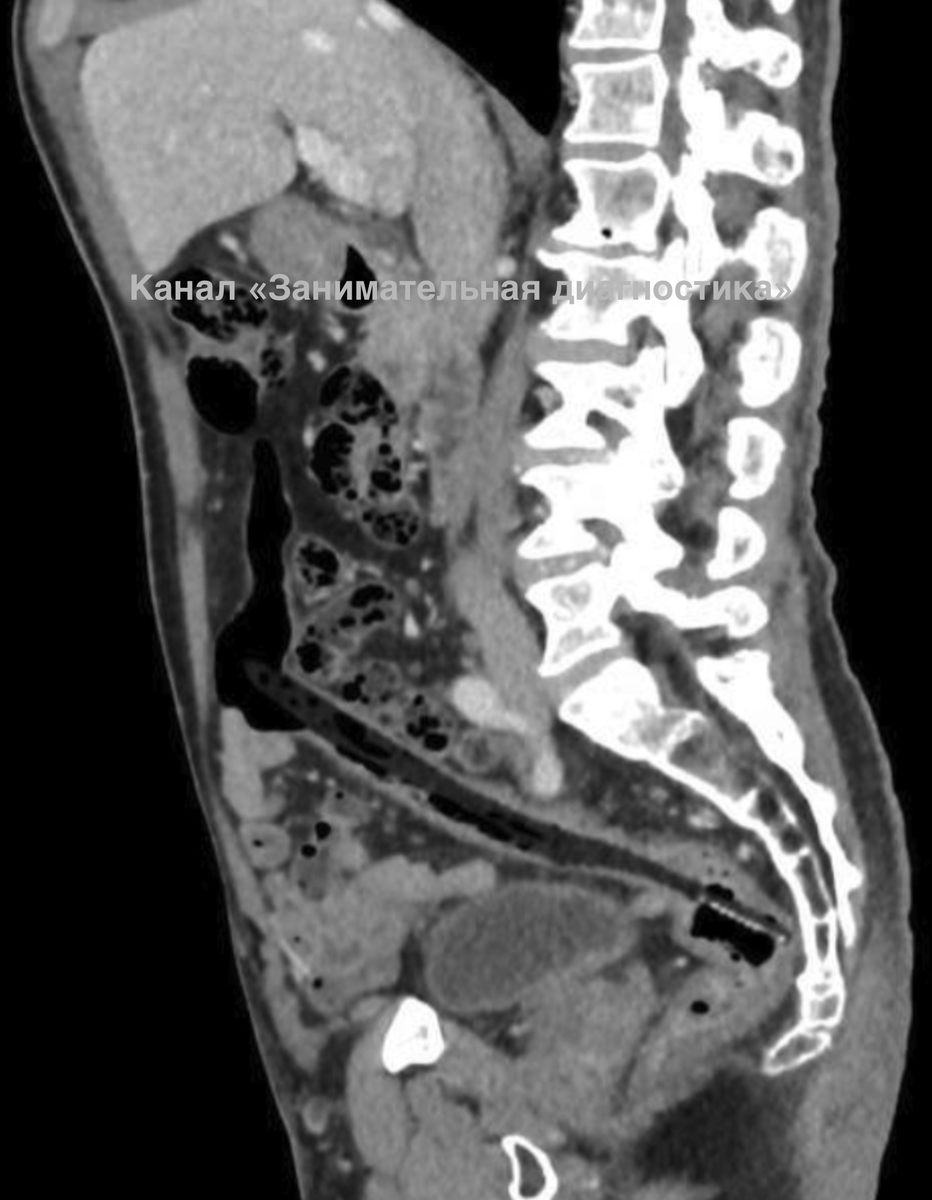

КТ мужчины. Выявлена зубная щетка в просвете прямой и сигмовидной кишки

На КТ выявлена зубная щетка в просвете прямой и сигмовидной кишки у пациента. Сам он ее достать не смог. Доктора смогли решить эту проблему.